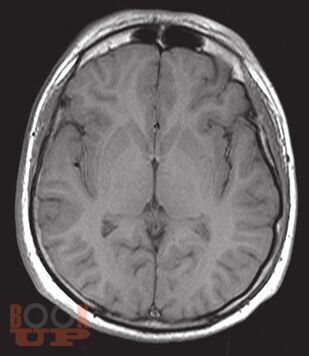

«Атлас нормальной анатомии магнитно-резонансной и компьютерной томографии головного мозга» посвящен актуальной проблеме нейроморфологии и краниологии — прижизненной макроскопической характеристике головного мозга и черепа с применением современных методов визуализации — магнитно-резонансной томографии и компьютерной томографии.

В Атласе представлены более 500 томограмм: магнитно-резонансные томограммы головного мозга, магнитно-резонансные ангиограммы головного мозга, магнитно-резонансные томограммы черепных нервов, компьютерные томограммы головного мозга, компьютерные ангиограммы сосудов головного мозга. Выполнена компьютерная реконструкция костей черепа, дана подробная информация об одном из сложнейших объектов черепа человека — височной кости.

Представленные томограммы могут заинтересовать специалистов в области магнитно-резонансной и компьютерной диагностики не только в качестве эквивалента нормы головного мозга, но и в пределах достаточно широкого диапазона индивидуальной анатомической нормы.